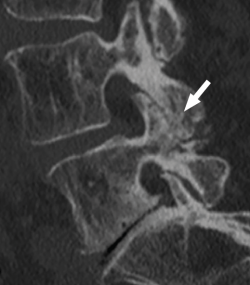

La TAC visualiza con bastante precisión el tejido óseo, siendo claramente superior a la RM para ello. También permite visualizar los tejidos blandos intra- y paraespinales, aunque la RM es muy superior en la evaluación de estos tejidos, por lo que está siendo desplazada por esta para el estudio de los problemas discales, degenerativos y radiculomedulares (Figura 11).

Figura 12. Tomografía axial computarizada de hernia discal. Reproducido de Gaillard(26).

Entre las principales indicaciones de la TAC, se incluirían la sospecha clínica de hernia discal (Figura 12)(26), la estenosis del canal vertebral lumbar, la fractura vertebral lumbar, los tumores vertebrales, la valoración posquirúrgica tras una cirugía de artrodesis vertebral lumbar y la sospecha de una sacroileitis en el contexto clínico de una posible espondiloartropatía inflamatoria. También es muy útil como herramienta auxiliar en determinados procesos diagnósticos, como por ejemplo en la biopsia de una zona sospechosa y en el diagnóstico postoperatorio de la correcta colocación de implantes en la columna vertebral.